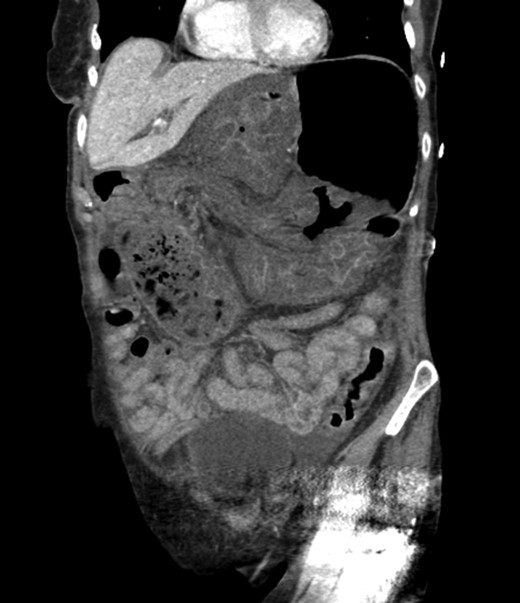

An 81-year-old female with a medical history of CAD with stents, hyperlipidemia, hypothyroidism, GERD, recent UTI, pancreatic cyst, constipation, anemia and leukopenia presented to the ED with a 1 day history of mild, diffuse and cramping abdominal pain. The patient was unable to give an accurate history, but the son at bedside supplemented this reporting that for several years the patient had been experiencing ill-defined abdominal discomfort. Physical exam showed a soft abdomen with mild tenderness and no evidence of peritonitis. A CT scan of the abdomen and pelvis with IV and PO contrast (Fig. 1) showed edematous changes to the mesentery of the small and large bowel with swirling of vessels indicative of internal hernia. The stomach was also noted to be distended with both air and fluid as a consequence of posterior compression by the hernia contents (Fig. 2). A surgical consult was obtained, a nasogastric tube and Foley catheter were placed, antibiotics were started, and the patient was taken for an exploratory laparotomy. Upon entering the abdomen through a vertical midline incision, 1.5 l of ascites was drained revealing a diffusely edematous mesentery. A large portion of the small bowel was seen to be herniated through the Foramen of Winslow (Fig. 3). A Kocher maneuver and division of the gastrocolic ligament were then performed to allow release of the herniated small bowel. It was at this time that, in addition to small bowel, a large portion of the ascending and transverse colon was noted to be herniated through the foramen of Winslow. The small bowel was also seen to be torsed about its own mesentery. Normal anatomy was restored and the bowel noted to be healthy and viable with peristalsis (Fig. 4). Due to the large size of the foramen after reduction and enlargement, it was deemed best to leave it open to prevent any further incarceration or strangulation. The abdomen was closed and the patient tolerated the procedure well. At a follow-up visit 2 months later, the patient had well-healed incisions, was doing well, tolerating a diet, and gaining weight appropriately.

Diagnosing an internal hernia is frequently accomplished using physical exam and CT imaging. Abdominal X-ray does have some nonspecific findings suggestive of internal hernia but is usually inadequate for diagnosis. Diagnosis of a foramen of Winslow hernia, however, is only accomplished in 10% of patients preoperatively [3]. As previously mentioned this diagnosis is rare and often presents with vague obstructive type symptoms. This likely contributes to the low occurrence of accurate preoperative diagnosis. However, several radiographic findings were seen in this patient that suggested a foramen of Winslow hernia preoperatively. First, there is visible swirling of the mesentery on the CT scan that is indicative of internal hernia (Fig. 1). Second, there are loops of small bowel that can be visualized between the IVC and the edge of the liver in a supra renal position along the lesser curvature of the stomach (Figs 1 and 2). When compared to a CT of the abdomen and pelvis obtained 4 years prior to presentation, there is actually evidence that this patient had a non-obstructing foramen of Winslow hernia at that time as demonstrated by bowel being visualized in the lesser sack (Fig. 5). These findings, especially small bowel along the lesser curvature of the stomach, are inconsistent with normal anatomy and strongly indicative a foramen of Winslow hernia.

CT abdomen and pelvis coronal view of foramen of Winslow hernia.